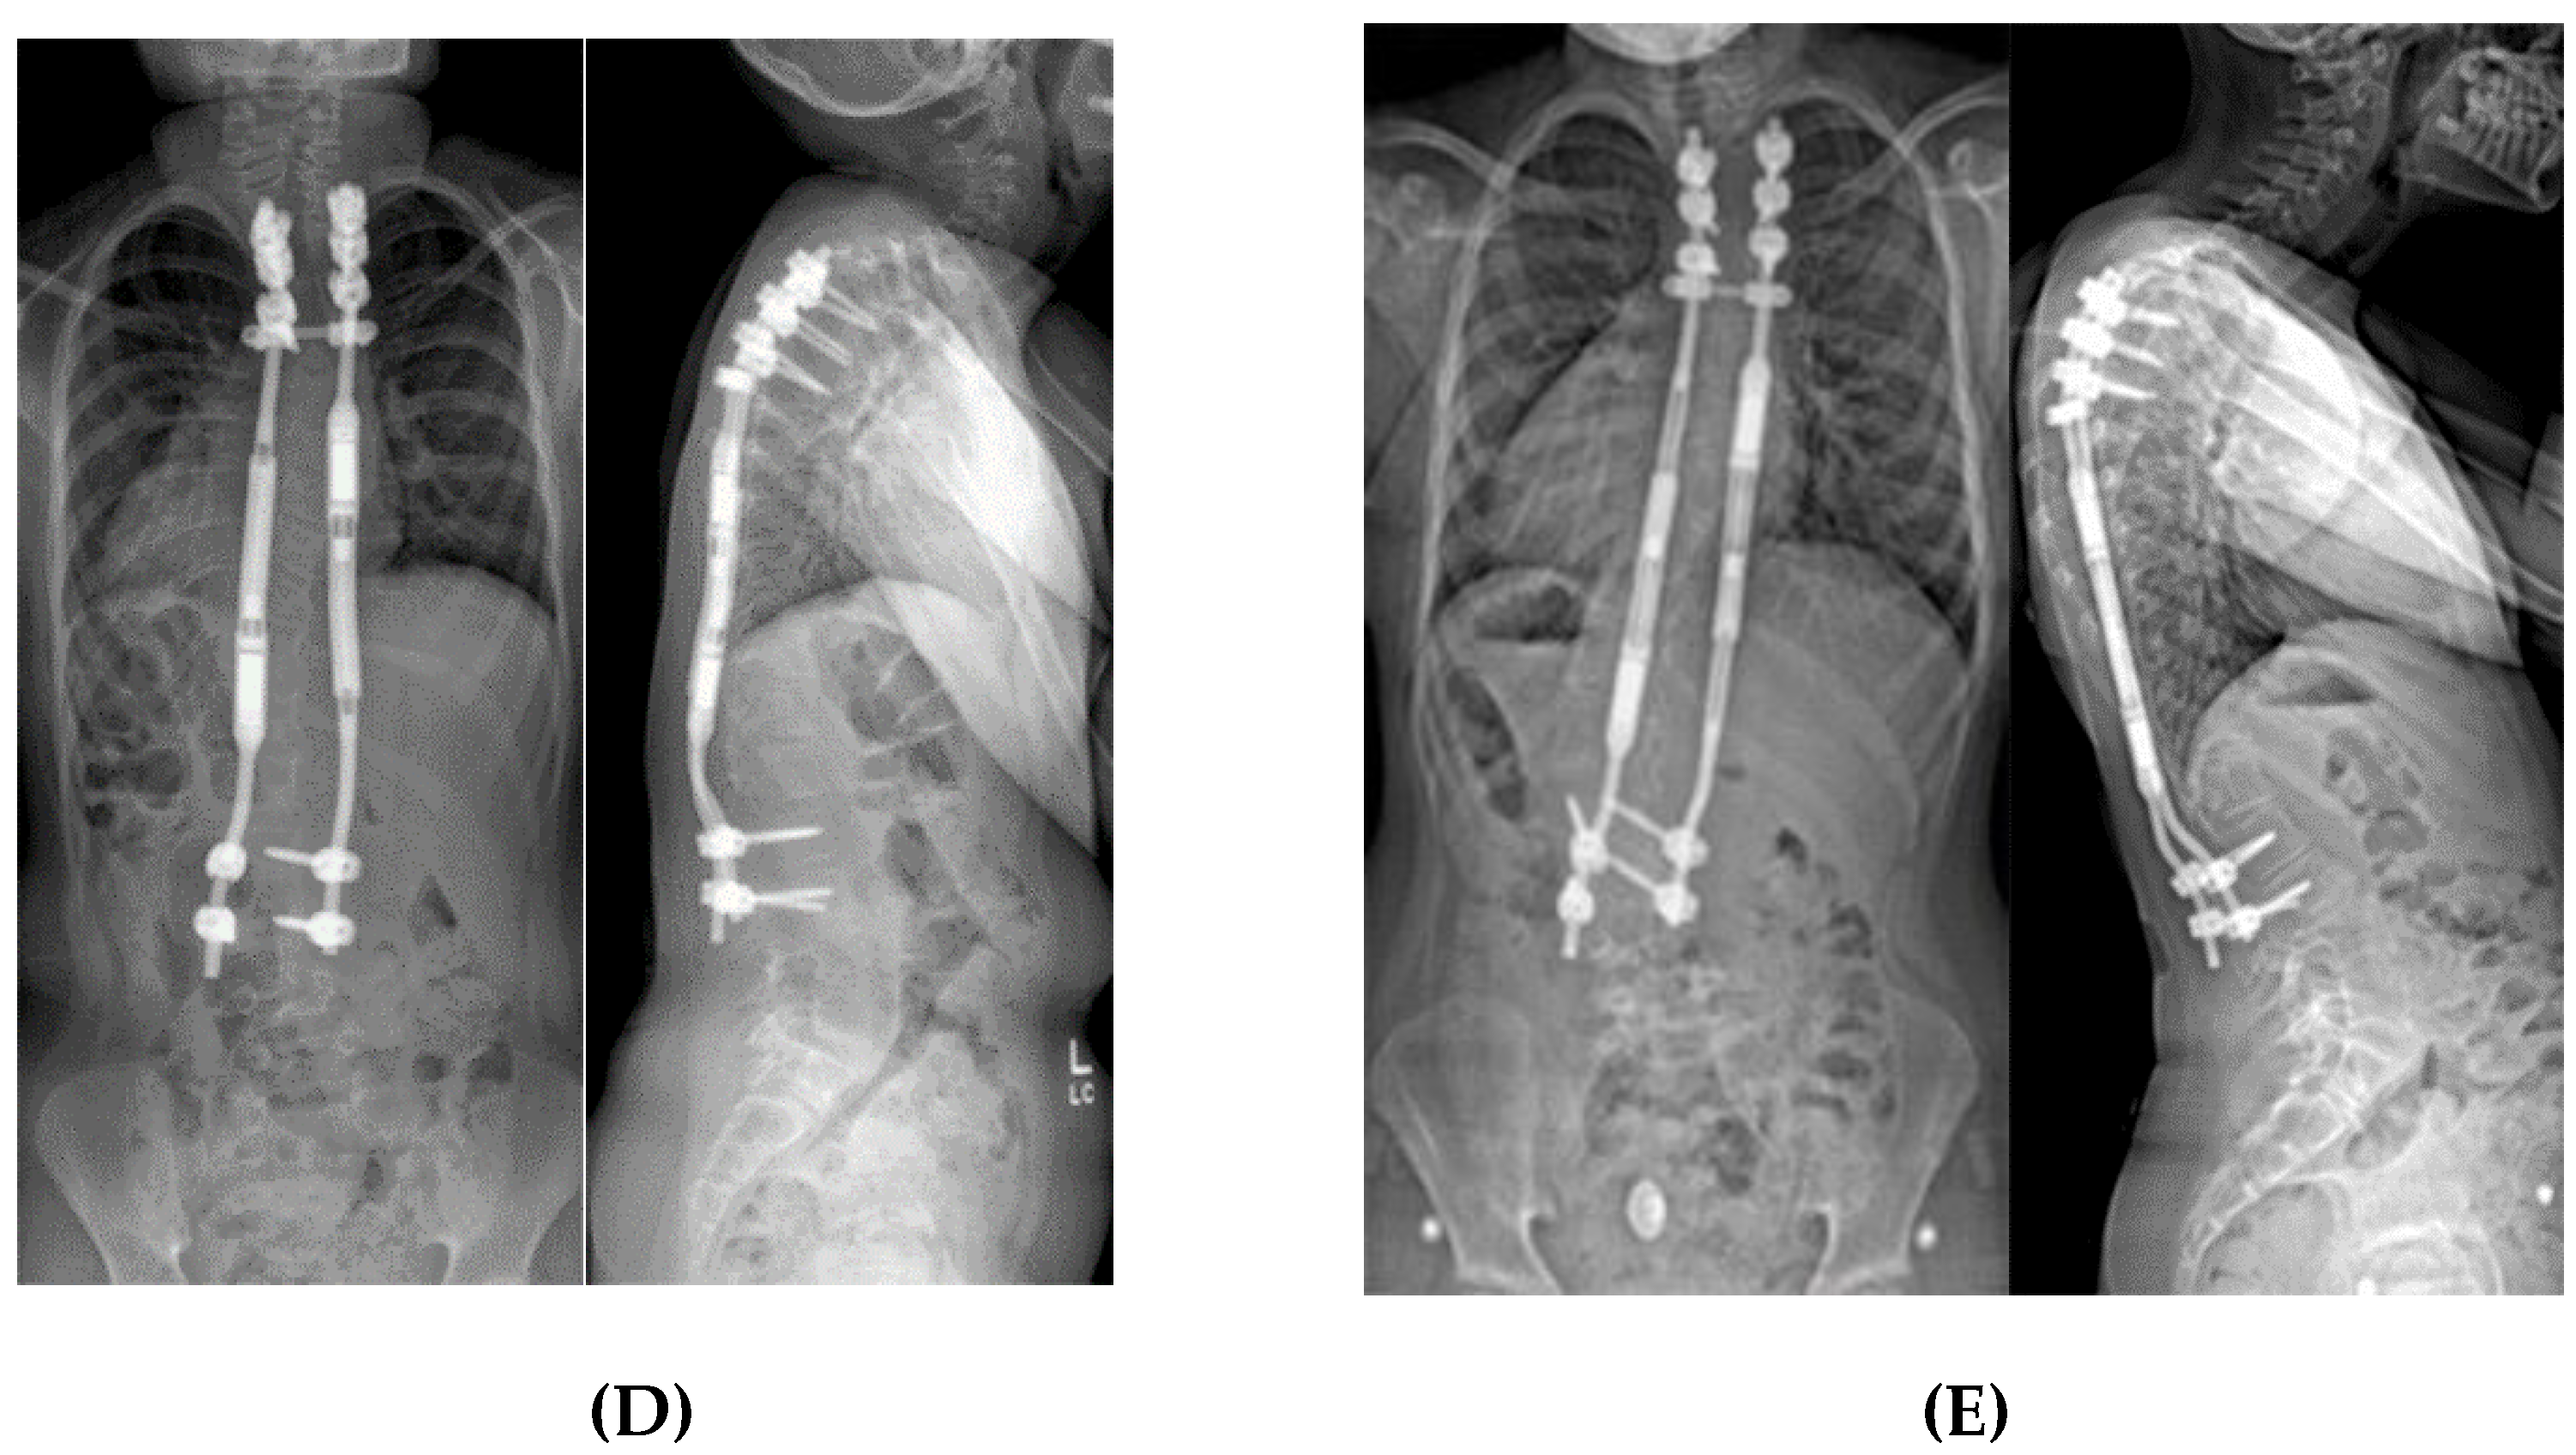

Figure 8.

(A) AP and lateral radiographs of a 10-year-old female with PWS deletion type with 103° curve. (B) AP and lateral radiographs 1 month later, after placement of non-fusion spinal instrumentation. Curve is 57°. (C) 18 months later, after 50mm of lengthening, curve is 25°.

Young children with severe infantile curves may need stabilization of the spine to allow for more symmetric chest development with growth. Typically, these are child too old for spinal casting but have substantial remaining growth with curves >50° and minimal flexibility/improvement in brace. If they cannot be maintained in brace, then an expandable implant serves to internally splint the spine. Early implant versions required manual distraction, typically performed every six months as an open procedure in the operating room (Figure 8). This strategy worked well for controlling the curve and maintaining spine growth, but with the potential complications related to surgical procedures. In 2014, expandable spinal rods became available that were magnetically actuated through the skin. The rods are lengthened every three months, using an external spinning magnet, which causes the magnet within the rod to rotate thereby lengthening the rod (Figure 4). Oore et al found that the average initial curve was reduced from 76° to 42° at time of implant surgery with no change in curve size over the subsequent two years of rod elongation [40].

Expandable implants, as a technique, have a life span of approximately five years, after which the ongoing process of spontaneous fusion along the section of the instrumented spine leads to stiffness and an inability to lengthen further [50,51]. Therefore, the goal is to manage the curve non-operatively until the child is 5–8 years of age, in order to “grow” the spine until at least 10 years of age. Unfortunately, the magnetically actuated rods only generate 42 pounds of axial force and may fail to generate enough force to elongate after several lengthening procedures. There are also issues related to titanium wear debris noted at the time of device removal [52]. Generally, these devices have made important improvements in the treatment of severe curves seen in young children with PWS. Usually, the construct is anchored with two vertebral levels above and below, but when there is any question of bone strength, three levels are fixated.